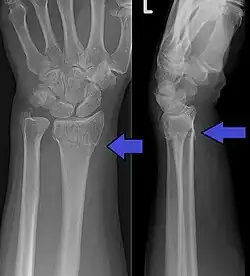

Diagnosis may be evident clinically when the distal radius is deformed, but should be confirmed by X-ray. The differential diagnosis includes scaphoid fractures and wrist dislocations, which can also co-exist with a distal radius fracture. Occasionally, fractures may not be seen on X-rays immediately after the injury. Delayed X-rays, X-ray computed tomography (CT scan), or Magnetic resonance imaging (MRI) can confirm the diagnosis.

Medical imaging

X-ray of the affected wrist is required if a fracture is suspected. Posteroanterior, lateral, and oblique views can be used together to describe the fracture.[5] X-ray of the uninjured wrist should also be taken to determine if any normal anatomic variations exist before surgery.[5]